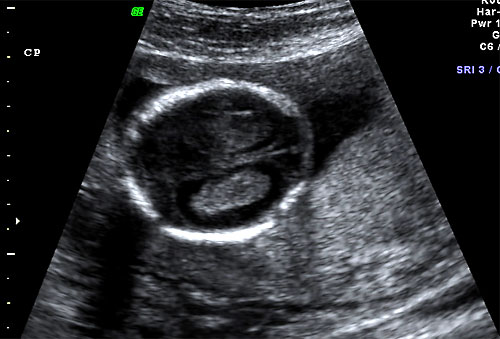

Normal 16 week bilateral ventricles |

Normal 16 week ventricular atria (lateral ventricle size) |